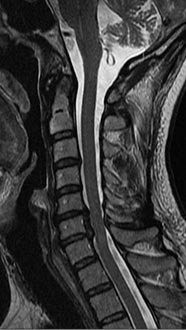

35 year old man presenting with severe neck pain with radiation down the right arm with right bicep weakness. MRI with large right C5-6 disc extrusion.